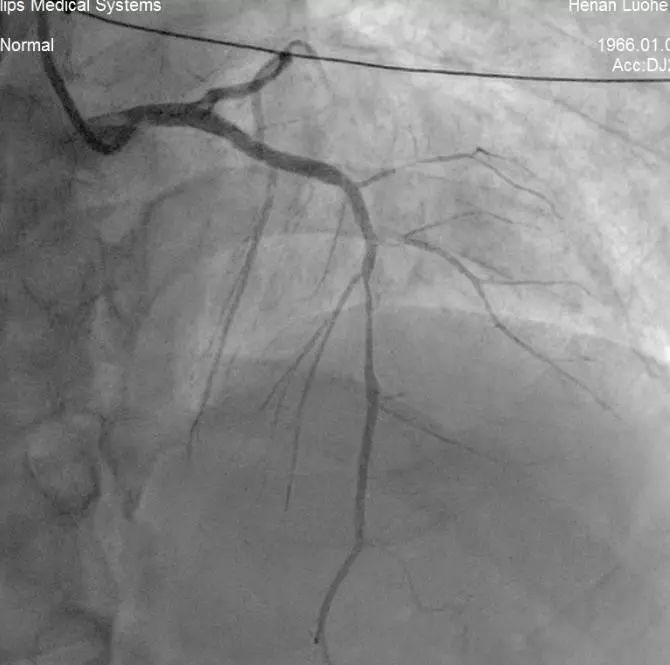

造影示左主干开口位置的闭塞病变,内有大块血栓

造影结果显示为左主干近段完全闭塞,患者处于休克状态,随时可能出现心脏破裂、恶性心律失常等并发症危及生命。

介入术后通畅的血管

手术结束后,患者梗死血管血流完全恢复,症状缓解,生命体征平稳,随即返回CCU病房密切监护治疗。